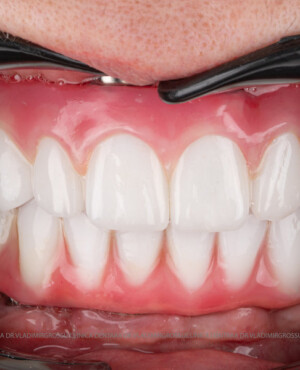

Caz 1

Caz 2